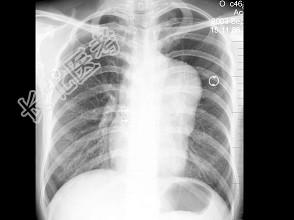

- 单项选择题女,32岁, 感胸闷、胸痛,X线检查如图, 最可能的诊断是 ( )

A、畸胎瘤

B、胸腺瘤

C、淋巴瘤

D、胸骨后甲状腺肿

E、神经源性肿瘤